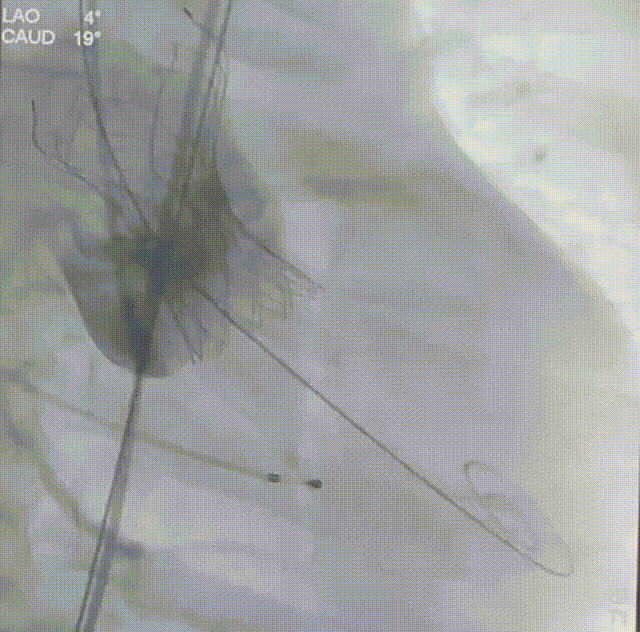

主动脉根部造影

22mm球囊预扩

瓣膜定位

瓣膜释放

瓣膜锚定

瓣膜完全释放

24mm球囊后扩

完成植入